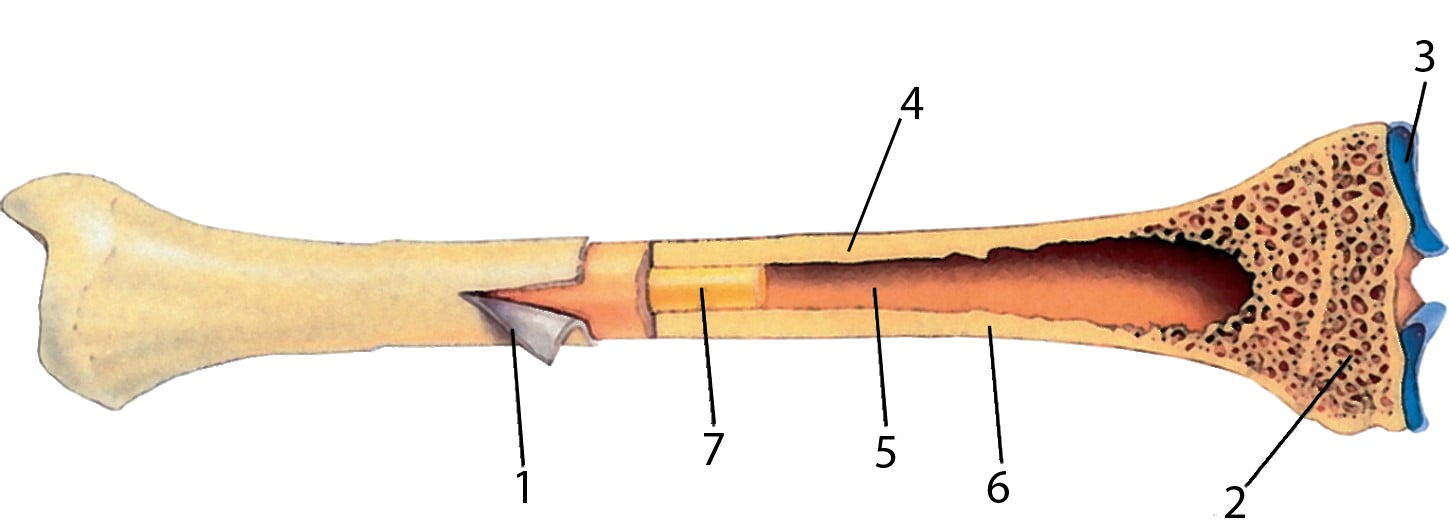

Изучение костного мозга: анатомия и функции